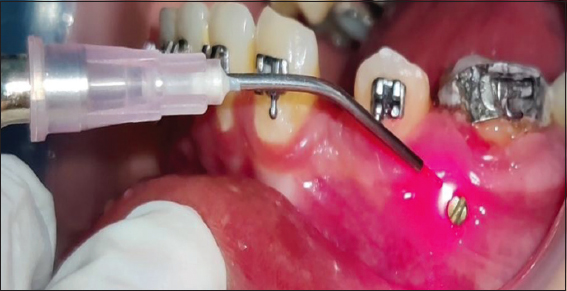

In the experimental group, implant site was irradiated with soft-tissue laser after placement, and in the control group, implant site was not irradiated with soft-tissue laser [Figure 5].

thumb

Figure 5: LLLI around the implant. LLLI: Low level laser irradiation